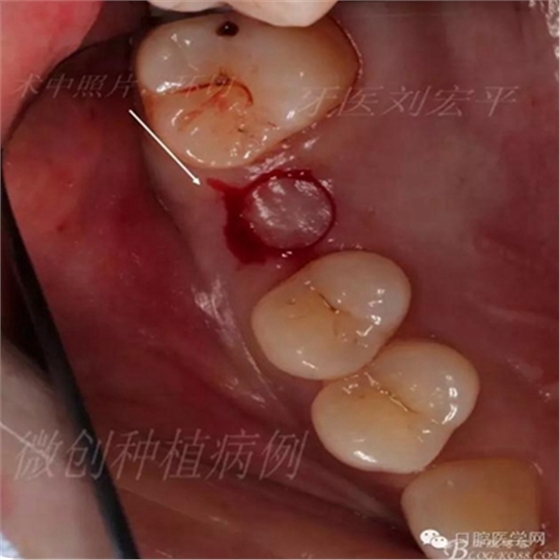

環(huán)切刀環(huán)切